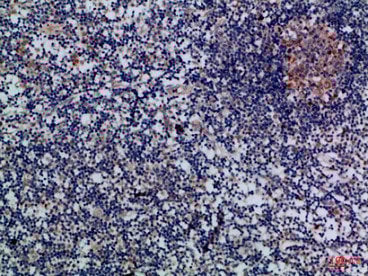

IHC (Immunohiostchemistry)

(Immunohistochemical analysis of paraffin-embedded Human-lymph, antibody was diluted at 1:100)